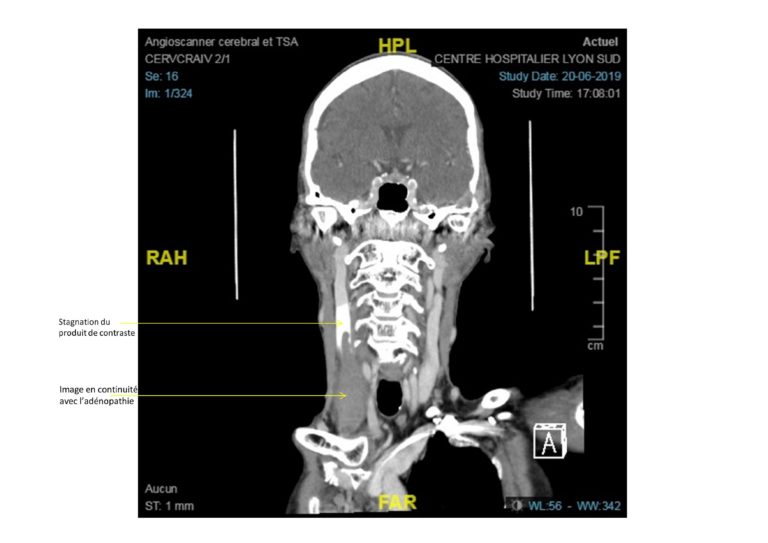

*e-Learning* – Mathilde P. âgée de 69 ans est traitée en première ligne depuis 1 mois pour un cancer du poumon épidermoïde multi-métastatique (cerveau, plèvre, ganglions, vertèbre…) par carboplatine-paclitaxel. L’écho-doppler réalisé, suite à l’échec